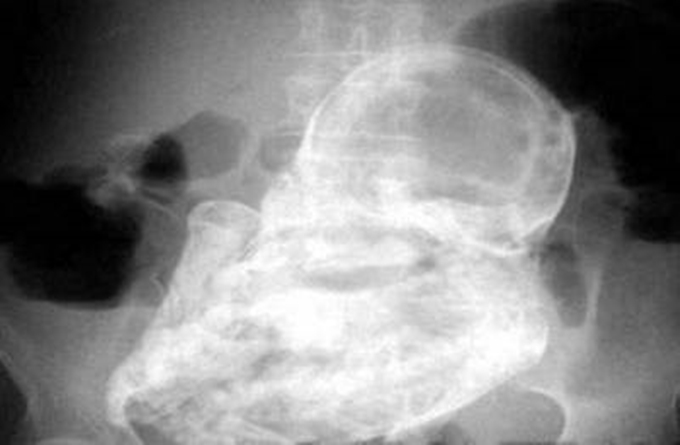

그리고 이어지는 사진은 X-Ray사진인데 아래 달린 멘트가 충격적이다.

인도에서 일어난 일로 소개된 멘트에서는 갑자기 고통을 호소하던 4살 아이를 부모가 병원에 데려갔더니 몸 안에서 태아가 있었다는 사실이다.

아이가 임신한 것은 아니고 원래 엄마의 뱃 속에서 쌍둥이로 태어났어야 했지만 일종의 기형으로 정상아의 몸에 기생한 채 태어나게 된 것이다.